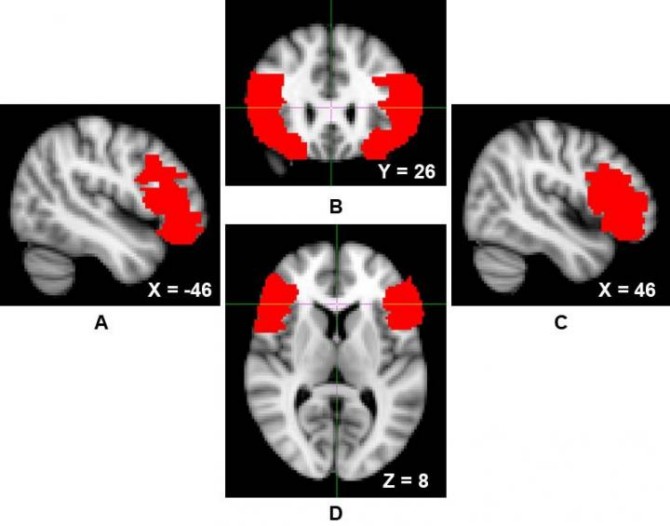

Over two structural MRI studies of “successful” psychopathic individuals, the researchers found that participants had greater levels of gray matter density in the ventrolateral prefrontal cortex, one of the brain regions involved in self-regulatory processes, including the down-regulation of more primitive and reactive emotions, such as fear or anger.

Over two structural MRI studies of 'successful' psychopathic individuals, the researchers found that participants had greater levels of gray matter density in the ventrolateral prefrontal cortex, one of the brain regions involved in self-regulatory processes. (Credit: VCU)

In both studies, the researchers observed that gray matter density in the ventrolateral prefrontal cortex — which the researchers call “a hub for self-regulation” — was positively associated with psychopathic traits.